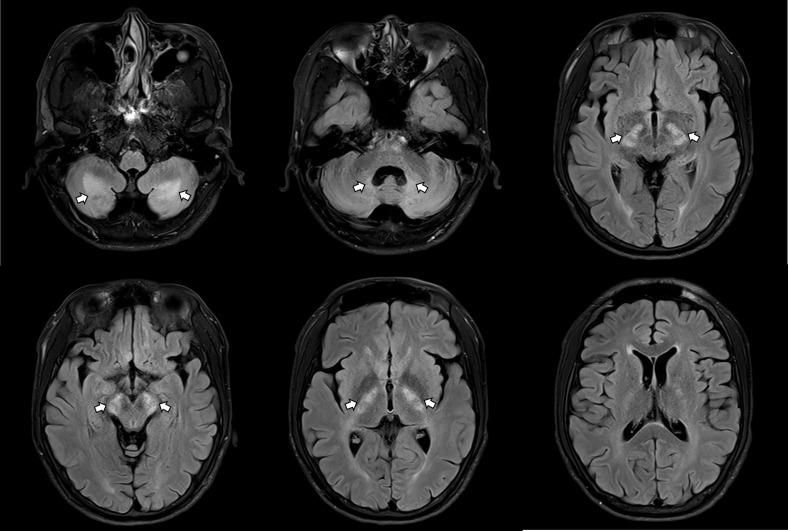

A 33-year-old man visited a psychiatric outpatient clinic with symptoms such as increasing distractibility and inattention, requesting an evaluation for adult ADHD. However, the absence of an ADHD history in childhood, coupled with progressive neurological symptoms and tendon xanthomas, led to further investigation. Comprehensive neurological assessments, including neuroimaging and genetic testing, ultimately diagnosed him with CTX. Treatment with chenodeoxycholic acid (CDCA) resulted in stabilization of cognitive function, although improvement in gait disturbances and tremors remained minimal.

一名33岁男性因注意力分散和注意力不集中等症状前往精神科门诊就诊,并要求对成人ADHD进行评估。然而,由于其童年时期无ADHD病史,再加上逐渐出现的神经症状和肌腱黄瘤,促使进行了进一步检查。包括神经影像学和基因检测在内的全面神经评估最终诊断他患有CTX。使用鹅去氧胆酸(CDCA)治疗使认知功能得以稳定,尽管步态障碍和震颤的改善仍然很小。